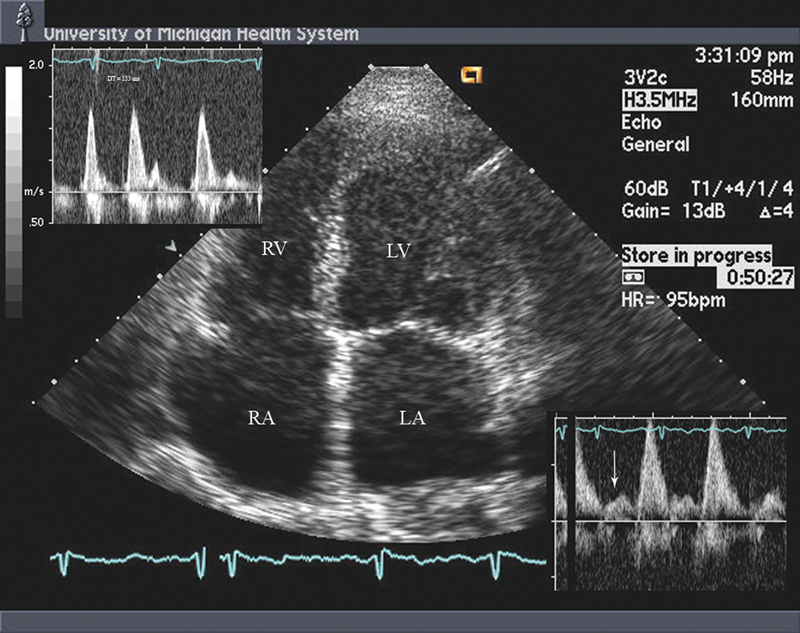

فحوصات تشخيصية لبعض امراض القلب والشرايين التاجية